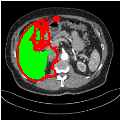

Our primary findings comparing the proposed model to baseline fully-supervised models when segmenting the liver from the LiTS dataset are reported in Table 1. The reported results demonstrate that our SAM-Mix model consistently achieves higher Dice scores compared to the fully supervised baselines as well as the two-stage SAM-PP method. Against U-Net, the best-performing fully supervised method, the SAM-Mix variant trained on 50 segmentation labeled slices (SAM-Mix-50), achieves a Dice score improvement of 5.9%. In terms of Hausdorff distance, while the fully-supervised baselines do slightly outperform SAM-Mix-5 and SAM-Mix-100, SAM-Mix-50 does achieve a lower Hausdorff distance by 22.38%. Qualitative evaluation as shown in Figs. 3 further affirms the superiority of SAM-Mix over baseline and existing fully-supervised methods as well as the two-stage SAM-PP variants. Furthermore, the boxplot visualization in Fig. 2 showcases consistently improved performance by SAM-Mix outperforming all the fully supervised and semi-supervised methods.

![]() |

| U-Net | nnU-Net | TransU-Net | SAM-PP-0 | SAM-PP-5 |

| SAM-PP-50 | SAM-PP-100 | SAM-Mix-5 | SAM-Mix-50 | SAM-Mix-100 |